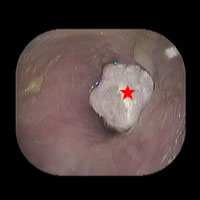

右外耳道真菌症(重症)

写真内の「★」が真菌(カビの一種)です。その周りに膿があります。飲み薬で治る病気ではありませんので、通院しなければなりません。耳の中(外耳道)を洗浄し、真菌を洗い流して真菌を殺す塗り薬を塗ります。21日目でほぼ治りま した。1週間で治る事もありますが、1カ月かかることもあります。

初診日